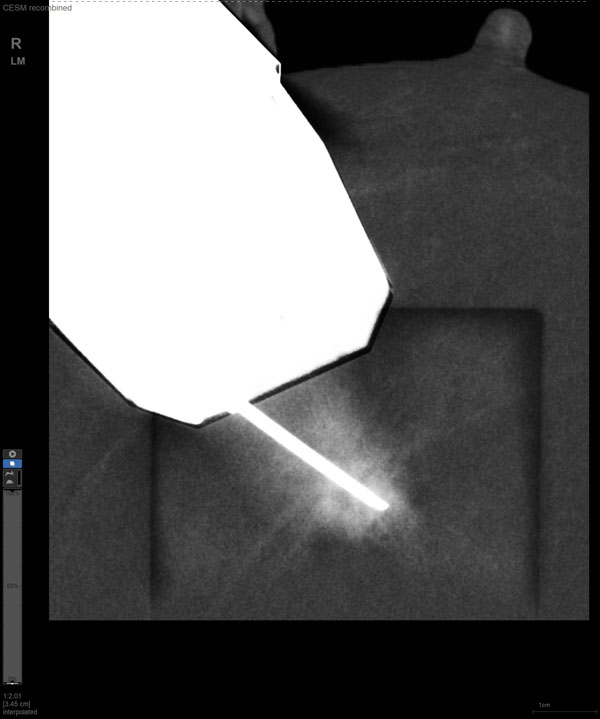

CEM引导下穿刺

某患者增强磁共振成像MRI显示肿瘤周边有活性,中心区域有组织坏死。为得到准确的病理结果,穿刺靶区需避开肿物坏死区域。在与患者主管医生充分讨论后,放射科医生为患者行CEM引导下穿刺活检术。术中,CEM检查肿物同样显示为环形强化,巧妙避开坏死区域后,穿刺靶区选择了肿物增强早期明显强化区域,术程顺利,仅用时15分钟。术后该患者病理结果为浸润性导管癌Ⅱ级。

国内首台具有数字乳腺断层摄影(DBT)和CEM引导下穿刺功能的X线机